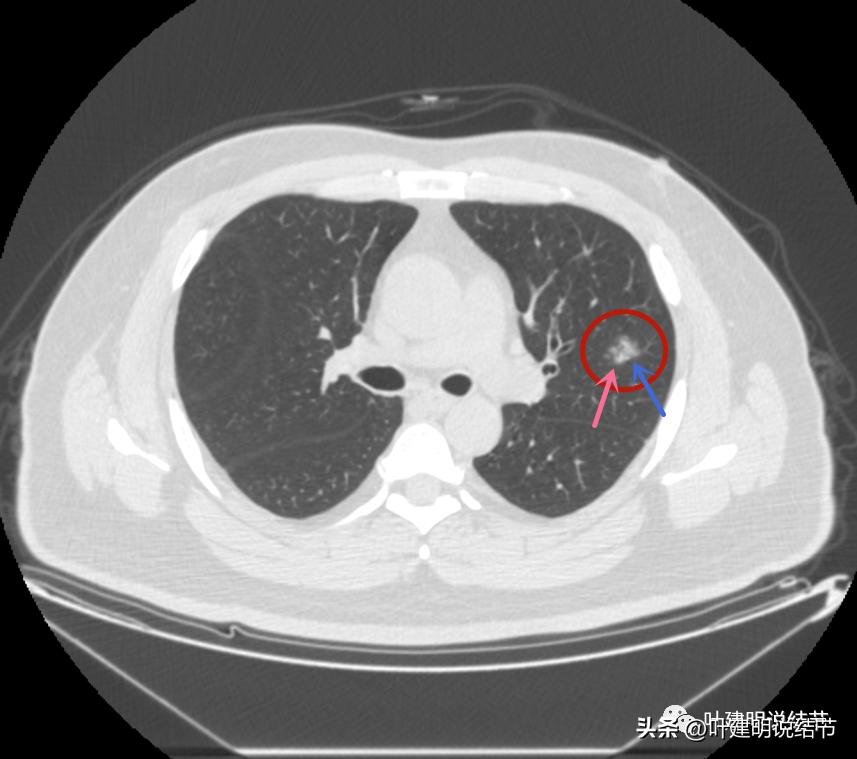

后续再看2022年8月的CT图像,有点惊掉下巴的感觉:

左上叶的病灶1、2、3都没有了!!!完全没有了!那当然说明是炎症性的,居然全部吸收了!

但左上病灶4仍在,形态也没有明显变化,无好转,也无明显进展。这是肿瘤性质的吗?虽然存在2年多了,但因为它的兄弟们都不见了,让我对它认定的肿瘤范畴也产生了怀疑,也许是纤维增生而已呢!

右上叶倒又出现了新的病灶:

右上病灶1:是新出现的,密度甚低,但轮廓较清,不典型增生吗?

右上病灶2:新出现的,整体轮廓较清,但感觉较散在,不致密,也不是圆形或类圆形,大概是炎性的吧!

2020年时同样位置是没有异常的:

还敢判定右上的病灶是恶性范围的不典型增生或原位癌吗?我是连左上病灶4都不敢了!还好,我觉得我们不必去纠结这几个病灶到底是不是肺癌或腺体前驱病变,反正至少风险很低,能随访就是了,肯定不能建议手术或消融等干预,也不需要穿刺活检。只要仍继续随访,半年吧!将结果交给时间来判断。